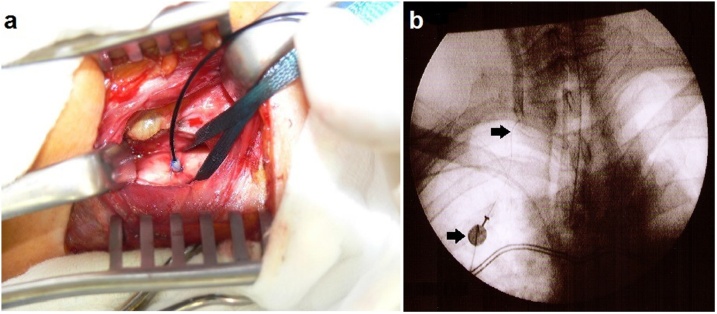

During the second in-patient stay from 2nd January 2011, a common carotid artery port catheter was implanted on both sides (Fig. 4). The intra-arterial catheter, to be implanted into the carotid arteria should not exceed 1.05 mm outside-diameter and its inner diameter should not be below 0.45.

Fig. 4.

a, b a) End-to-side implantation of the intra-arterial Jet-Port Allround catheter, b) Contrast imaging of carotid artery through implanted Jet-Port catheter.